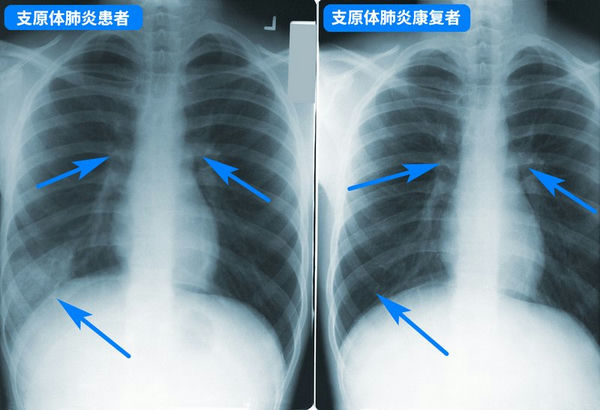

支原體肺炎胸透片

支原體肺炎***般并不嚴重,但要小心預防病情加重,盡早就醫,如持續發燒5天以上、劇烈咳嗽不止,則***定要就醫,以評估肺部是否受影響,以及是否存在并發癥。兒童支原體肺炎***般用阿奇霉素等大環內酯類藥物,但因為亞洲地區濫用藥物引起的耐藥性問題,很可能效果不佳,需要中途換藥,具體應該遵醫囑。